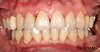

CAS DE TRAITEMENT PARODONTAL 1